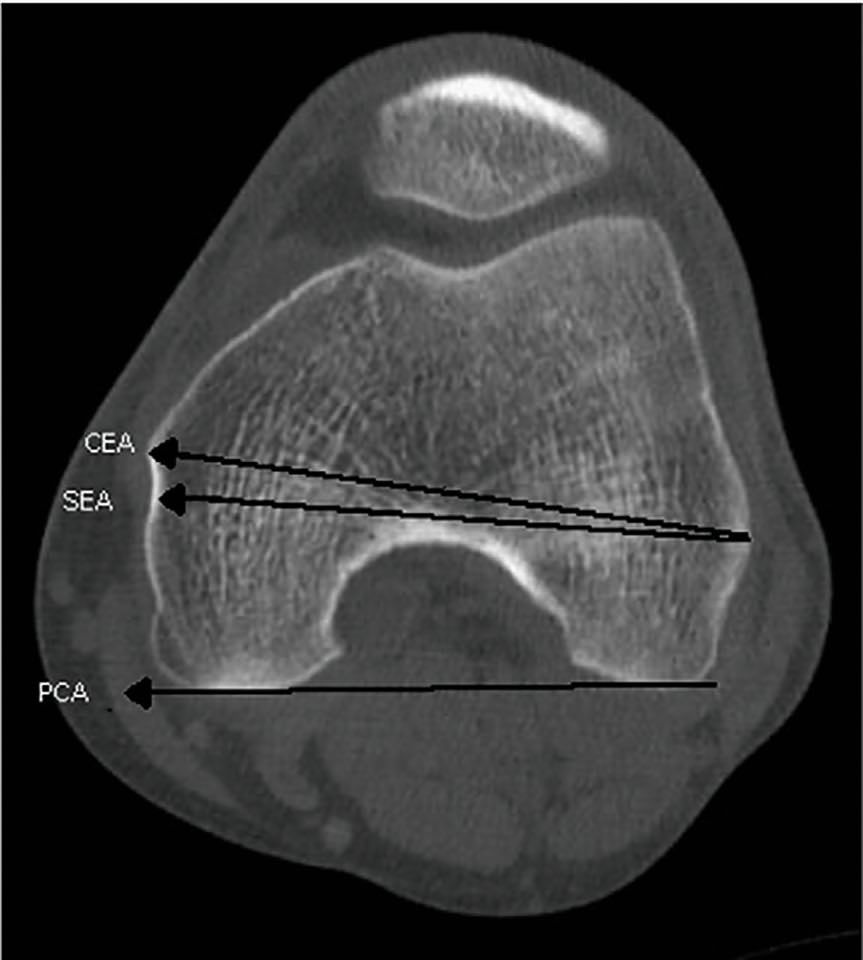

varus positioning of the trochlea to match that of a patient will allow even in cases of severe dysplasia, a normal entry of the patella into the trochlea groove. This approach is markedly different from typical TKA surgery in which the rotation of the femur is determined by the importance of flexion and extension gap balancing. Matching of the extension and flexion gap is aided by the three degree external rotation of the femur secondary to a ninety degrees tibial cut. Whilst this three degrees external rotation has reduced markedly the need for lateral release in total knee arthroplasty, it does not address well the very abnormal orientation of most patients with PFA who will have historic lateral maltracking and different tissue tensions related to the patella in comparison to total knee replacement patients. The third and final point that the surgeons will use to orientate the position of the trochlea component having decided its size and varus valgus orientation, will be the point used to determine rotation of the implant. Here is another point of controversy, should it be the local anatomy (the trochlea itself and anterior distal femur immediately adjacent to the trochlea) or the regional anatomy (that is the posterior condyles, epidcondylar access or whitesides line) (figure 3).

This debate is a continuation of the discussion between TKA surgeons and the developing thoughts of PFA surgeons regarding trochlea component orientation. TKA methods call for a balanced flexion and extension gap which as indicated above, are tied to a tibial cut perpendicular to the long axis. To compensate for the natural tibial plateau varum, the femoral component is externally rotated when the knee is flexed to 90°. It is often taught that the aim in TKA is the ‘the grand piano’ sign that is produced when the anterior cut is at 3° of external rotation (2)The grand piano sign is consistently produced when surgeons use this technique to cut 3° of external rotation relative to the posterior condyle access or by resection parallel to the surgical epicondylar access (figure 4a). The butterfly sign (figure 4b) is produced by resection with 0° of external rotation relative to the posterior epicondylar axis (3).

One might imagine the grand piano sign would be desirable with PFA however it should be noted that PFA, is not one third of a TKA and operative techniques differ very significantly as does the surgical approach. The rational for external rotation in TKA is not to improve patella tracking, but to balance the flexion and extension gaps and therefore this technique may not pass directly to surgery of the patellofemoral joint. I believe that the trochlea should be orientated independently of the tibial femoral joint line or the anatomical axis of the femur and replicate only the orientation of the patients trochlear based on the patients anatomy. This debate still develops and therefore Farr has suggested some recommendations for the rotational position of the trochlear component.